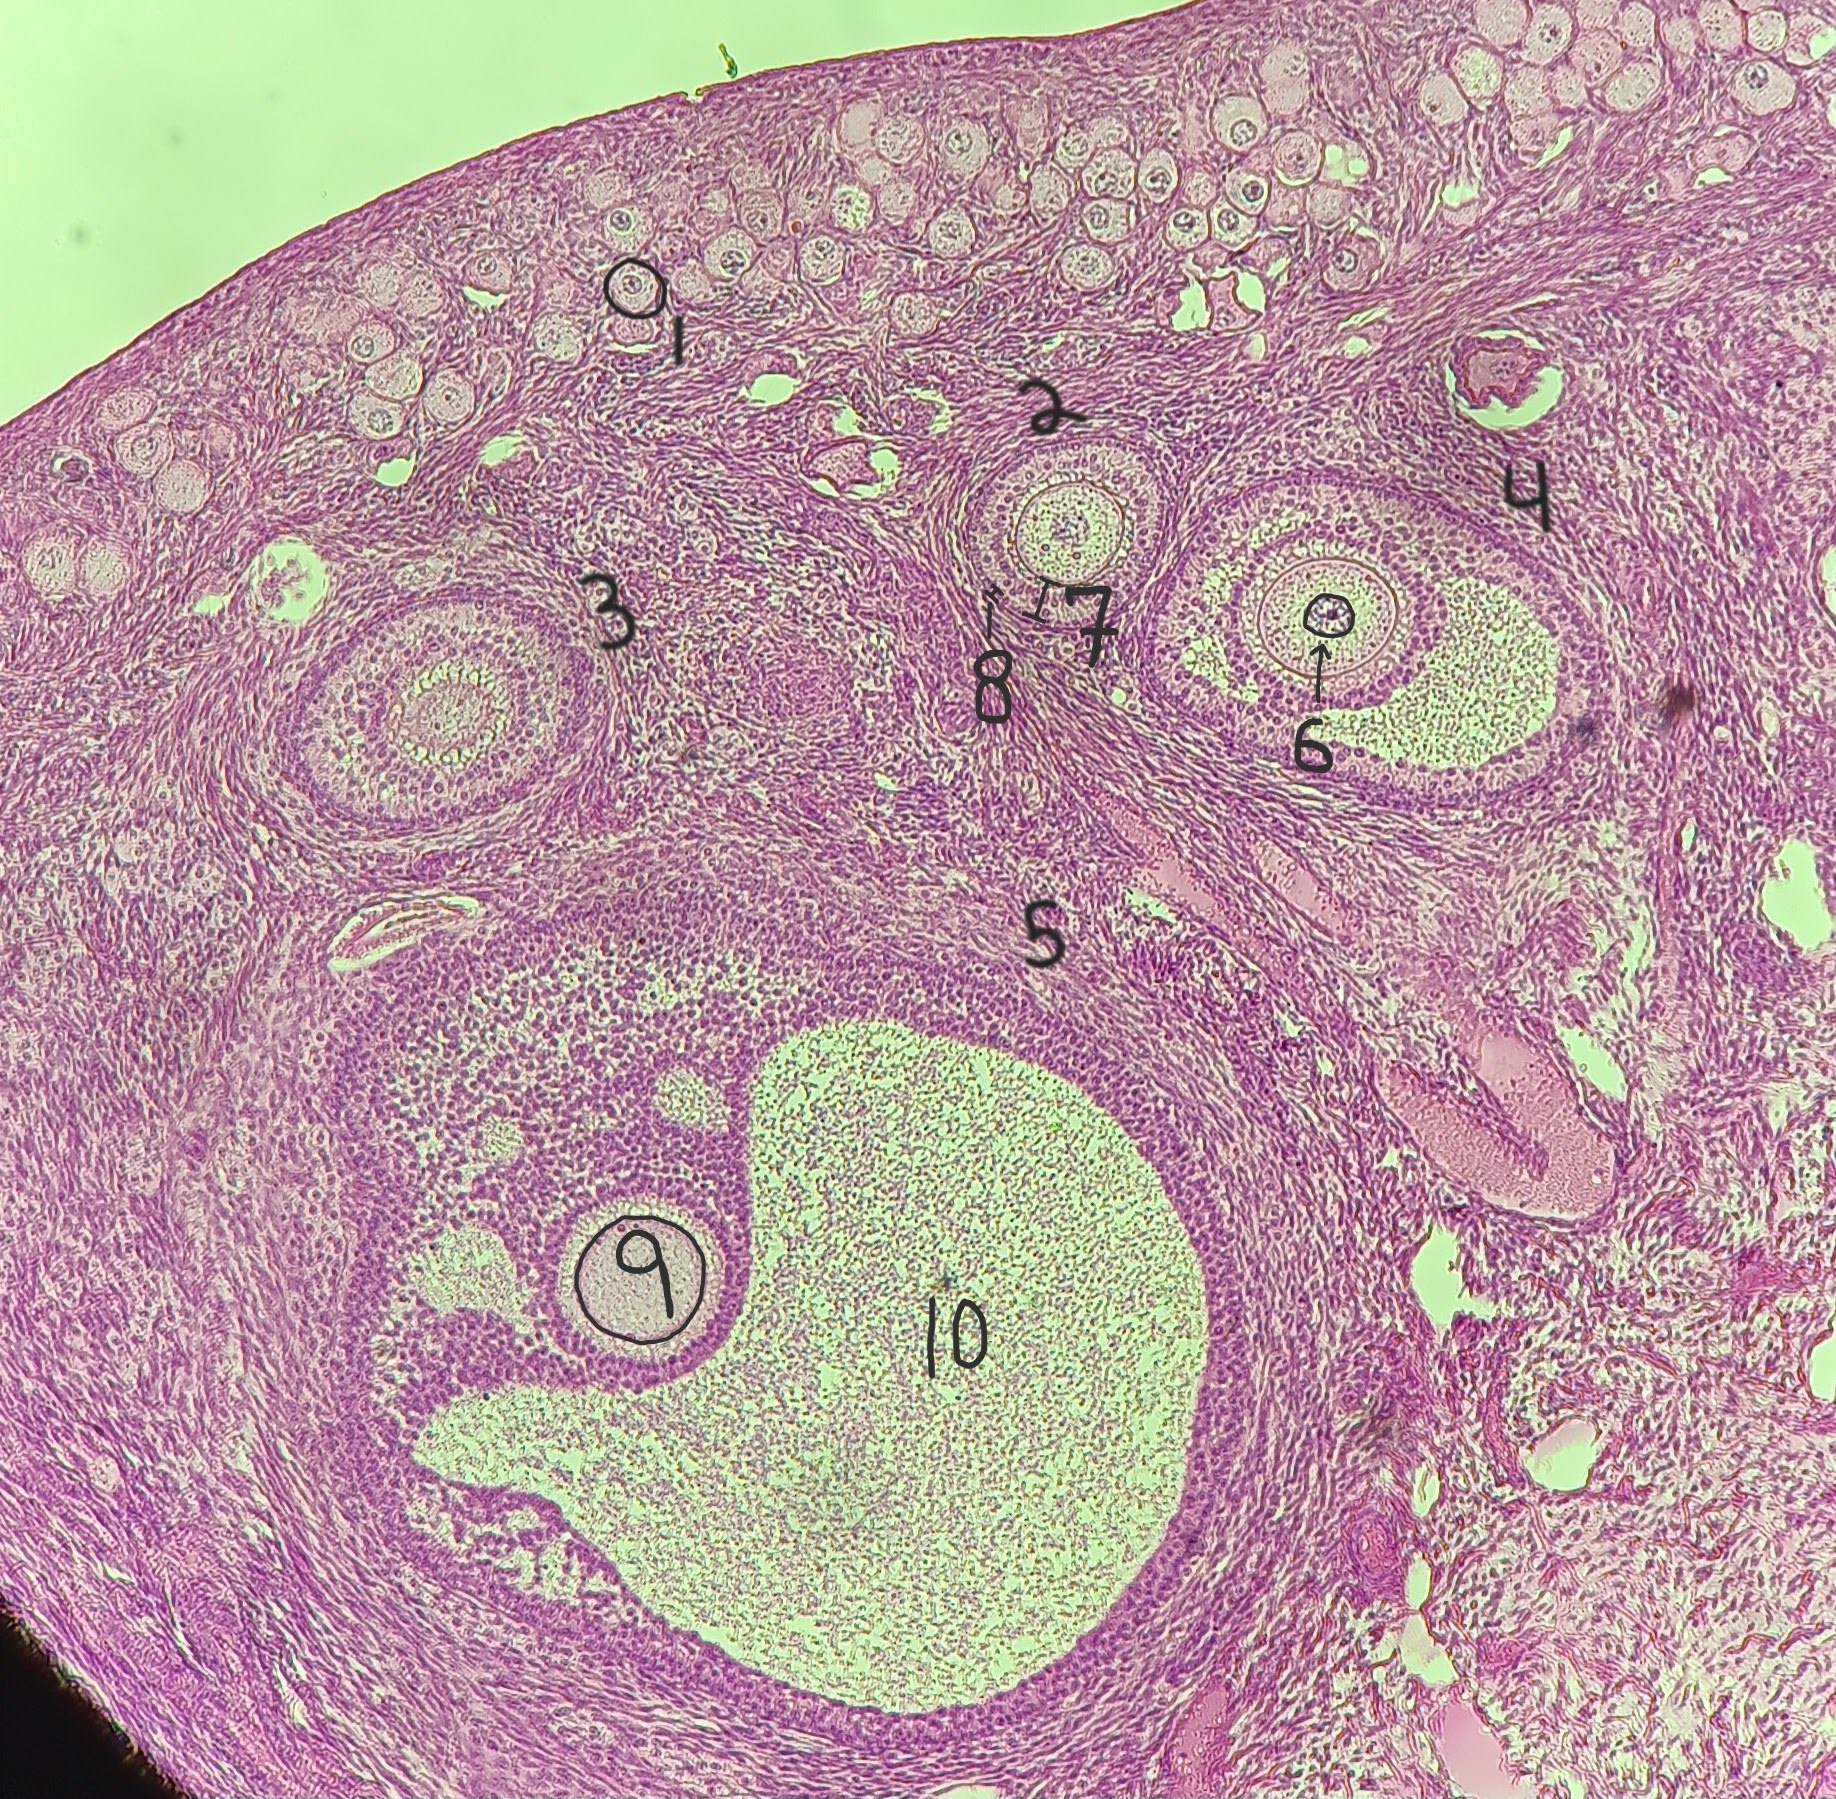

Primordial follicle

1

Primordial follicle

Primordial follicle

1

Primary follicle

2

Primary follicle

Primary follicle

2

Secondary follicle

3

Secondary follicle

Secondary follicle

3

Tertiary follicle

4

Tertiary follicle

4

Mature follicle

5

Mature follicle

Mature follicle

7

Antrum

10

Zona pellucida

9

Theca folliculi

8